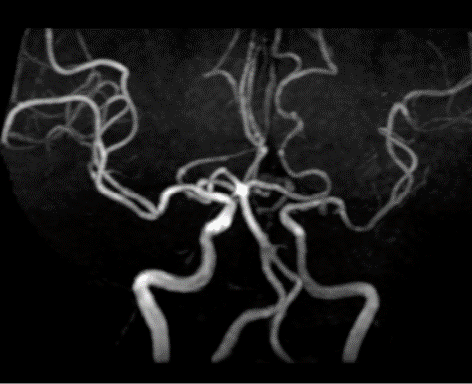

颅脑MRA

波科支架怎么样径技-弓上病例大赏|第205期·放疗后症状性颈动脉狭窄支架置入治疗一例_https://www.jmylbn.com_新闻资讯_第5张

波科支架怎么样径技-弓上病例大赏|第205期·放疗后症状性颈动脉狭窄支架置入治疗一例_https://www.jmylbn.com_新闻资讯_第6张